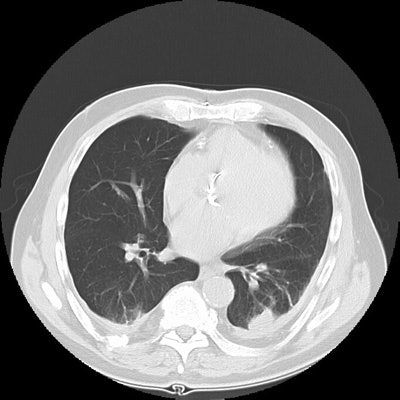

Rounded atelectasis:

The images show bilateral posterior pleural thickening. Within the left posterior lung a rounded pleural based mass-like opacity into which lung markings radiate can be identified. The left major fissure is displaced posteriorly. The lesion has remained stable for many years. The findings are consistent with rounded atelectasis. (Click small images to enlarge)